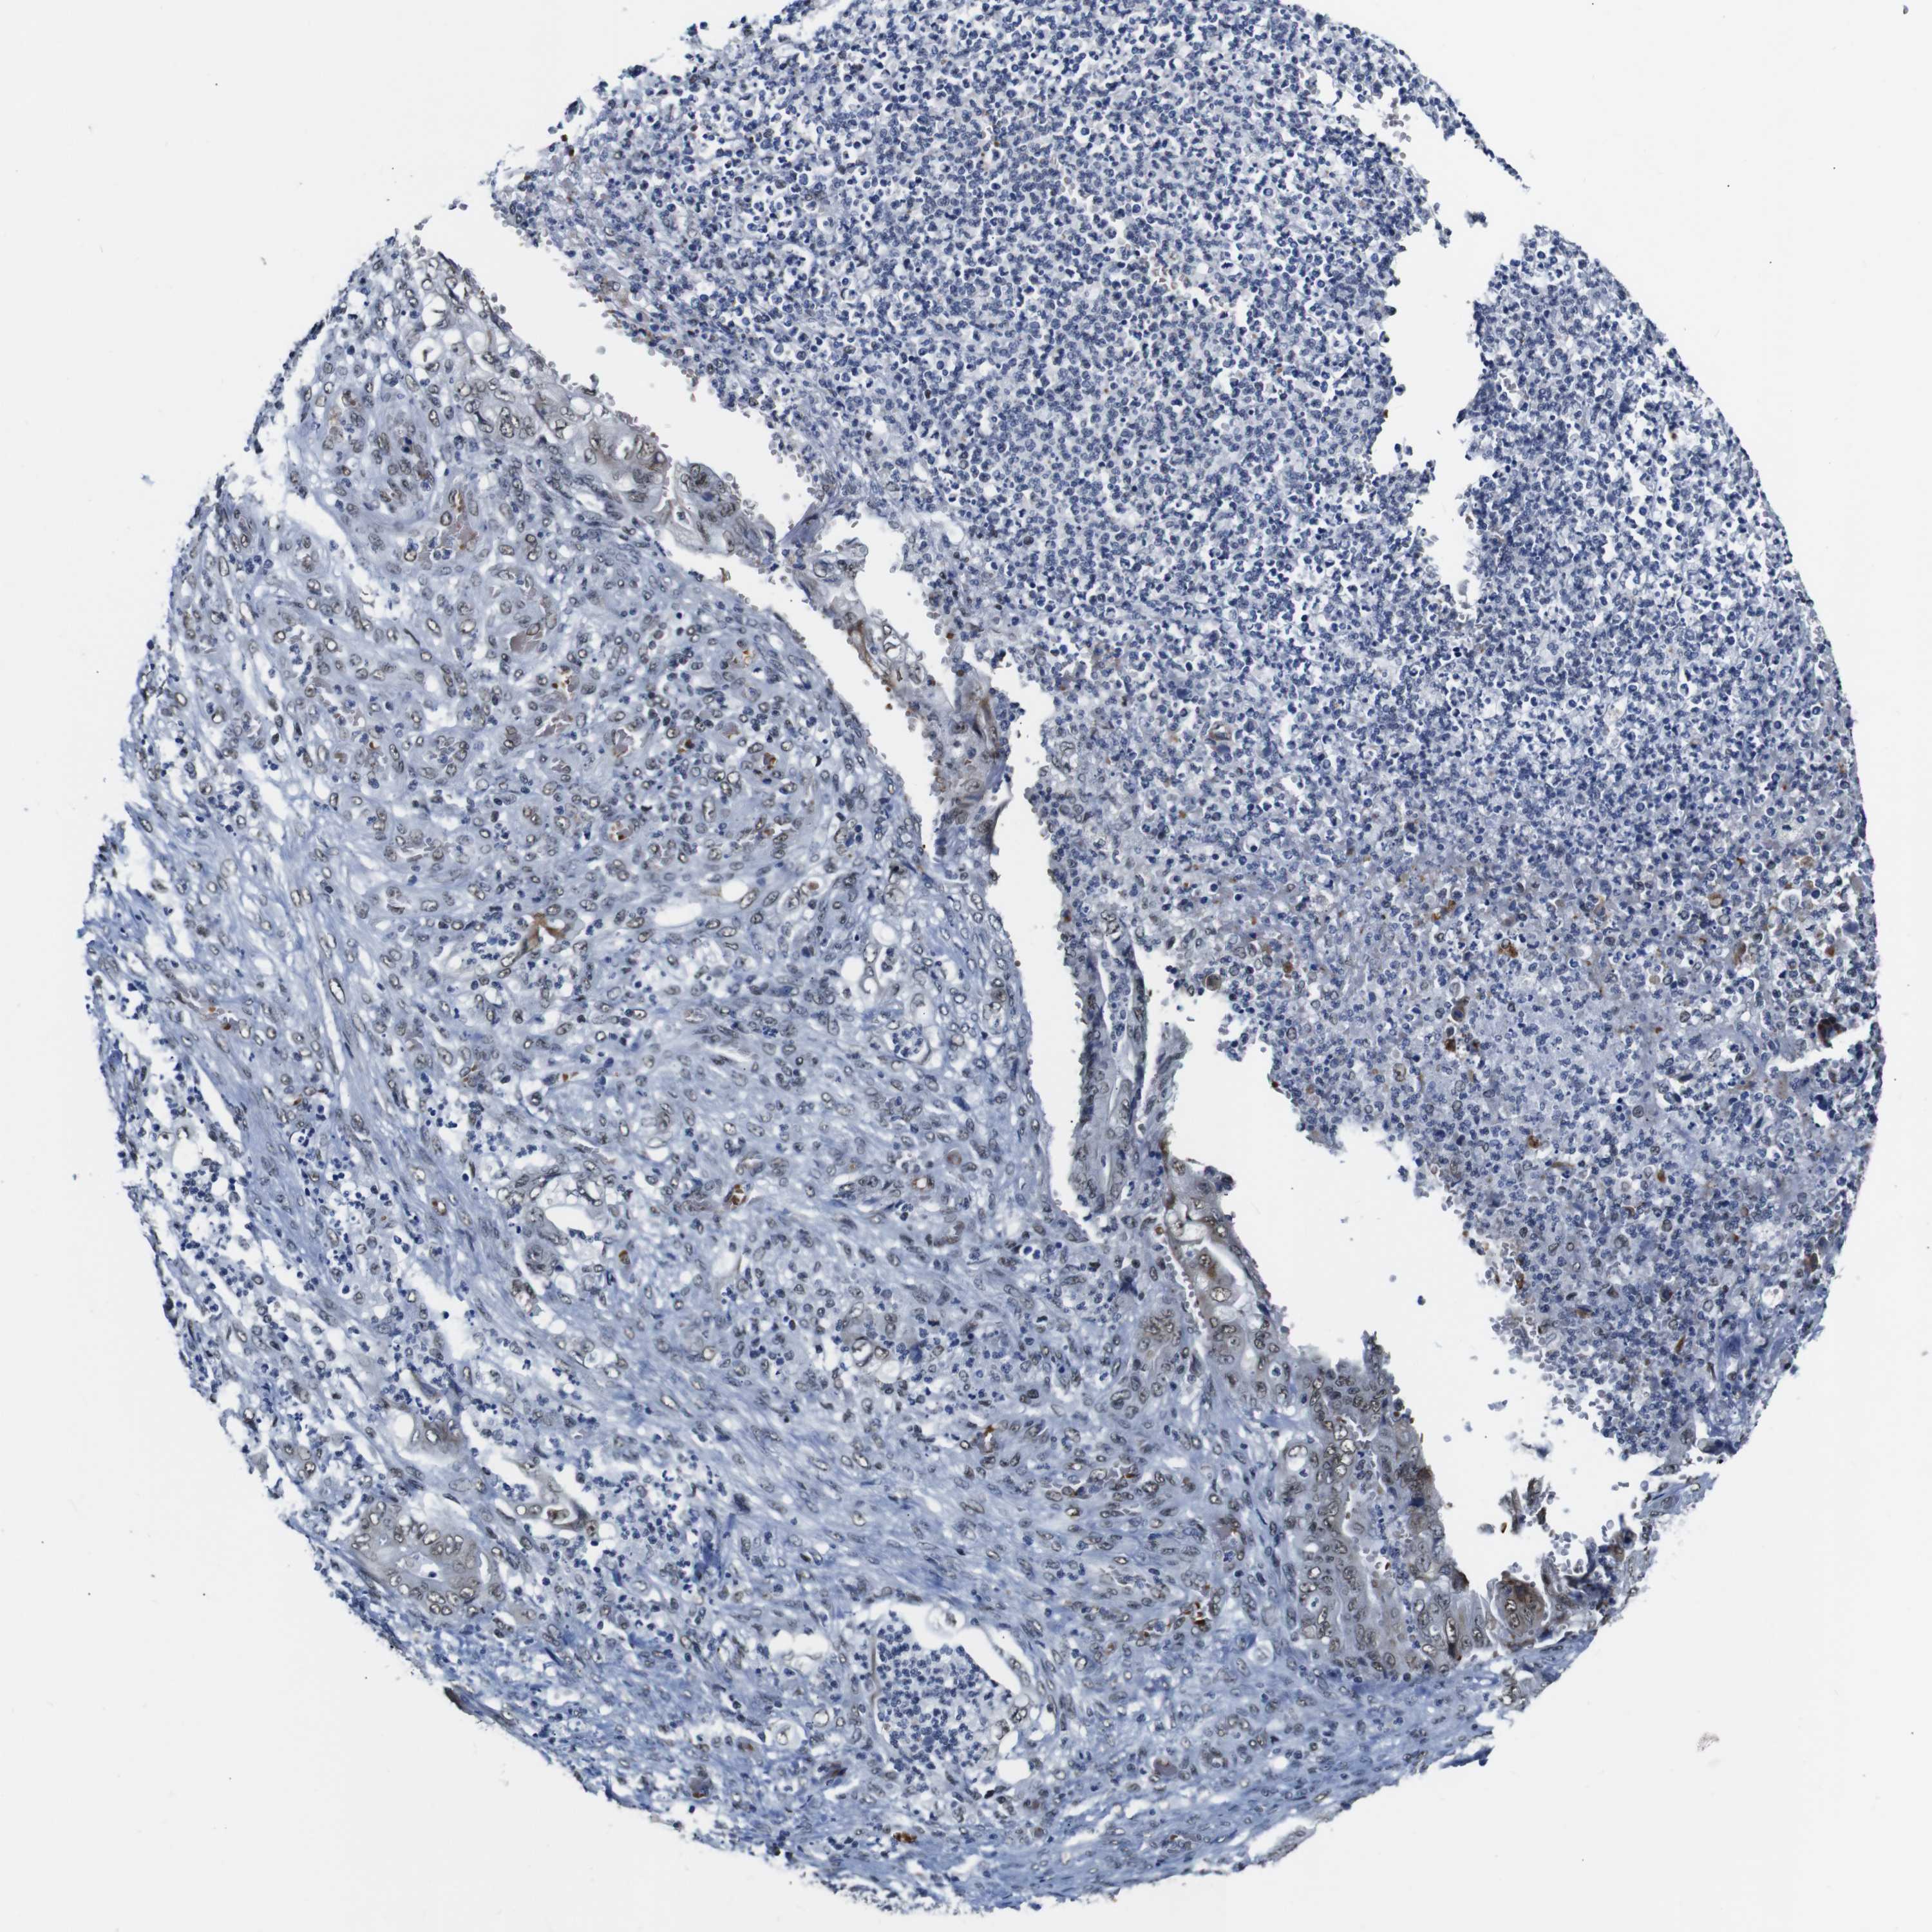

STOMACH CANCER - Protein expressioni

A mouse-over function shows sample information and annotation data. Click on an image to view it in a full screen mode. Samples can be filtered based on level of antibody staining by selecting one or several of the following categories: high, medium, low and not detected. The assay and annotation is described here.

Note that samples used for immunohistochemistry by the Human Protein Atlas do not correspond to samples in the TCGA dataset.

Antibody stainingi

Antibody staining in the annotated cell types in the current human tissue is reported as not detected, low, medium, or high, based on conventional immunohistochemistry profiling in selected tissues. This score is based on the combination of the staining intensity and fraction of stained cells.

Each image is clickable and will lead to virtual microscopy that enables deeper exploration of all samples and also displays staining intensity scores, fraction scores and subcellular localization as well as patient and tissue information for each sample.

Antibody HPA012545

Staining

High

Medium

Low

Not detected

Intensity

Strong

Moderate

Weak

Negative

Quantity

>75%

75%-25%

<25%

None

Location

Nuclear

Cytoplasmic/membranous

Cytoplasmic/membranous,nuclear

Adenocarcinoma, NOS

Adenocarcinoma, High grade